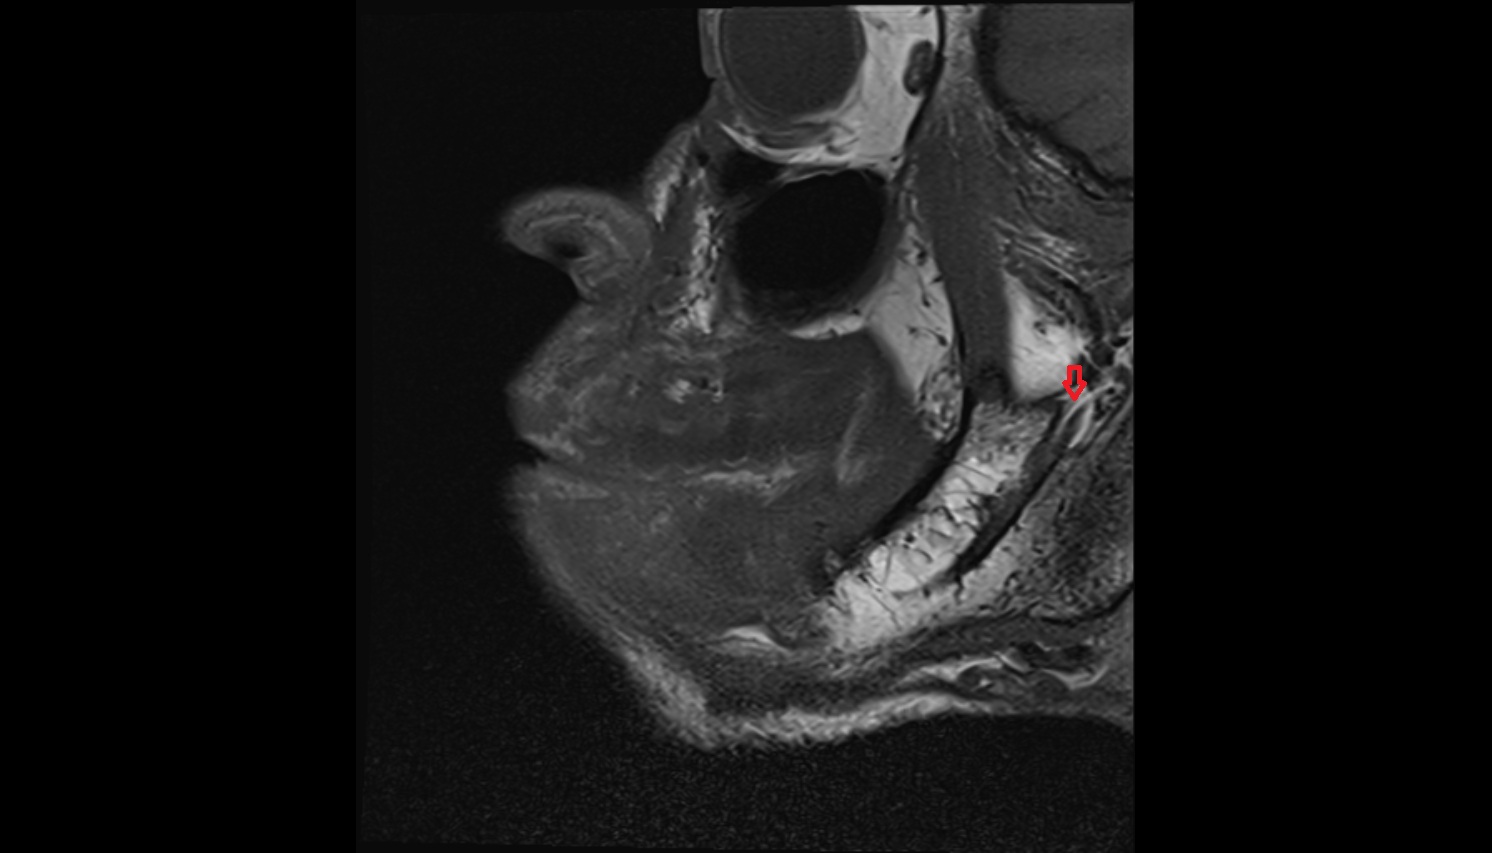

- Temporomandibular joint

- Articular disc of temporomandibular joint

- Articular eminence

- Mandibular condyle

- Mandibular fossa

- Superior head of lateral pterygoid muscle

- Inferior head of lateral pterygoid muscle